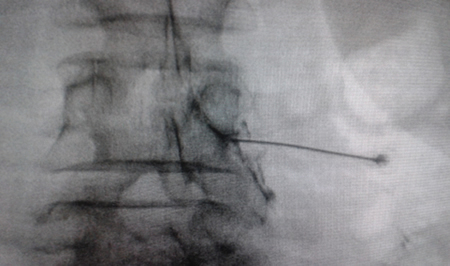

Access by transforaminal route is the most widely used (4). The patient is placed in prone position with an abdominal pillow to reverse physiological lordosis. The most commonly used RF needles or cannulas are 20 or 22 G diameter and 98 mm long with 0.5 or 1 cm active tip. Following asepsis with alcoholic chlorhexidine and placement of sterile fields, radiological approaches in anteroposterior, oblique and lateral incidence are performed. In anteroposterior incidence and moving the arc in cranio-caudal direction, the double arc of the lower vertebral edge is deleted. In oblique incidence between 20 and 30 degrees ipsilateral to the DRG to be treated, the classic image described as “Scotty Dog” will be displayed, which is the result of bringing the articular facets and the spinous process closer to the contralateral side. The entry point will then be immediately below the pedicle. After local anesthesia with 1 % lidocaine, the needle will be inserted following a tunnel vision and will not advance beyond half of the pedicle in this projection to prevent neural injury. In lateral projection, it will be inserted into the roof of the neuroforamen (Figures 1 and 2) but the final location will be determined by sensory-motor nerve stimulation. Sensory stimulation is to cause paresthesia or pain in the affected territory with stimulation between 0.3-0.6 v. During motor stimulation fasciculations can be caused in the affected territory with a voltage of twice that necessary to cause paresthesia. If an intraganglionar denervation, promulgated by some authors, is desired, both sensory and motor stimulation will be positive at less than 0.3 v. As this is a more painful procedure, it is advised to administer local anesthetics after the painful stimulus and before treatment. The impedance should be kept below 450 ohms, which is achieved by infusing saline before proceeding with RF (4). The use of contrast is good practice, as it rules out the intravascular and intrathecal position of the radiofrequency cannula.

Fig. 1. Lateral radiological view showing a radiofrequency cannula at the anterosuperior angle or roof of the neuroforamen, approximate topography of the dorsal root ganglion